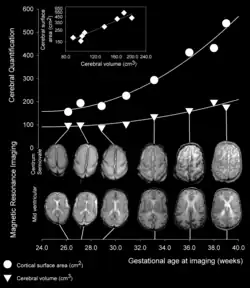

Faltung (Gyrierung)

Dreieck (▼): Gehirnvolumen

Kreis (⚫): Hirnoberfläche

Raute (◆) im kleineren Schaubild: Verhältnis von Oberfläche zu Volumen

Die Großhirnrinde zeichnet sich bei vielen Säugetieren durch zahlreiche Windungen (lateinisch-griechisch Gyri, Singular Gyrus), Spalten (lateinisch Fissurae, Singular Fissura) und Furchen (lateinisch Sulci [cerebri], Singular Sulcus) aus. Die Faltung dient der Vergrößerung der Oberfläche: beim Menschen beträgt diese etwa 1800 cm². Bei der Furchung des Cortex unterscheidet man eine Primärfurchung, die bei allen Individuen annähernd gleich ist, von einer Sekundär- und Tertiärfurchung, die so individuell wie ein Fingerabdruck sein können.